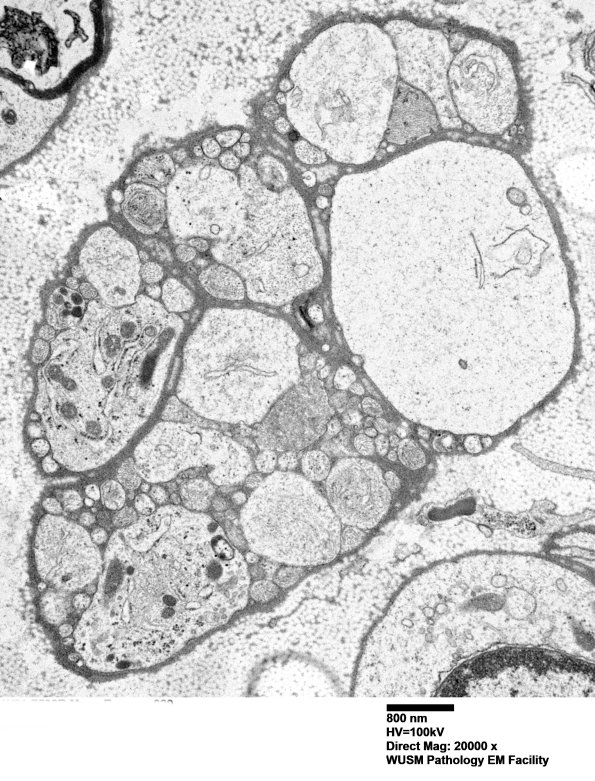

Typical demyelinated axons of this size do not usually occur with multiple accompanying vacuolated Schwann processes. The subcellular organelles are numerous in some processes and contain ribosomes. (electron micrograph)